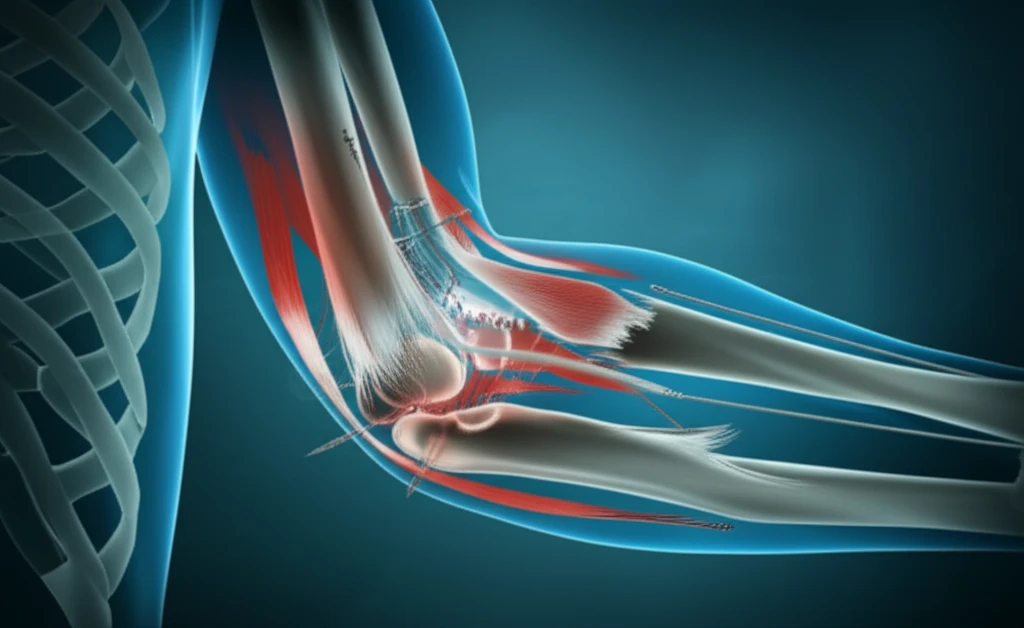

Elbow injuries, especially those affecting the medial collateral ligament (MCL), can significantly impact daily life and athletic performance. The MCL, comprised of the anterior bundle (aMCL), posterior bundle (pMCL), and transverse ligament, is crucial for elbow stability, particularly against valgus stress—the force that pushes the elbow outward.

The mini-open aMCL plication is designed to restore stability to the elbow by addressing laxity in the anterior bundle of the medial collateral ligament. The procedure involves a few key steps, starting with a thorough arthroscopic evaluation.

- aMCL Plication: The aMCL is plicated—folded and secured—using suture anchors inserted into the humerus at the ligament's original attachment point. This effectively tightens the ligament.